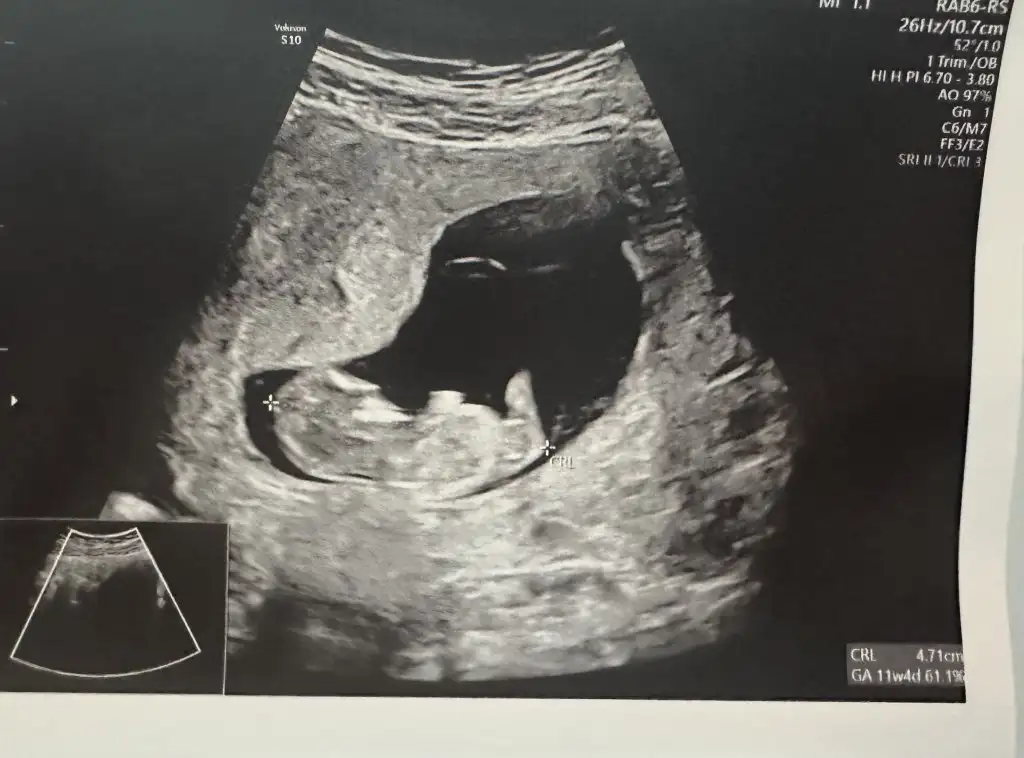

Beklenen doğum 8 OcakHafta-11+4